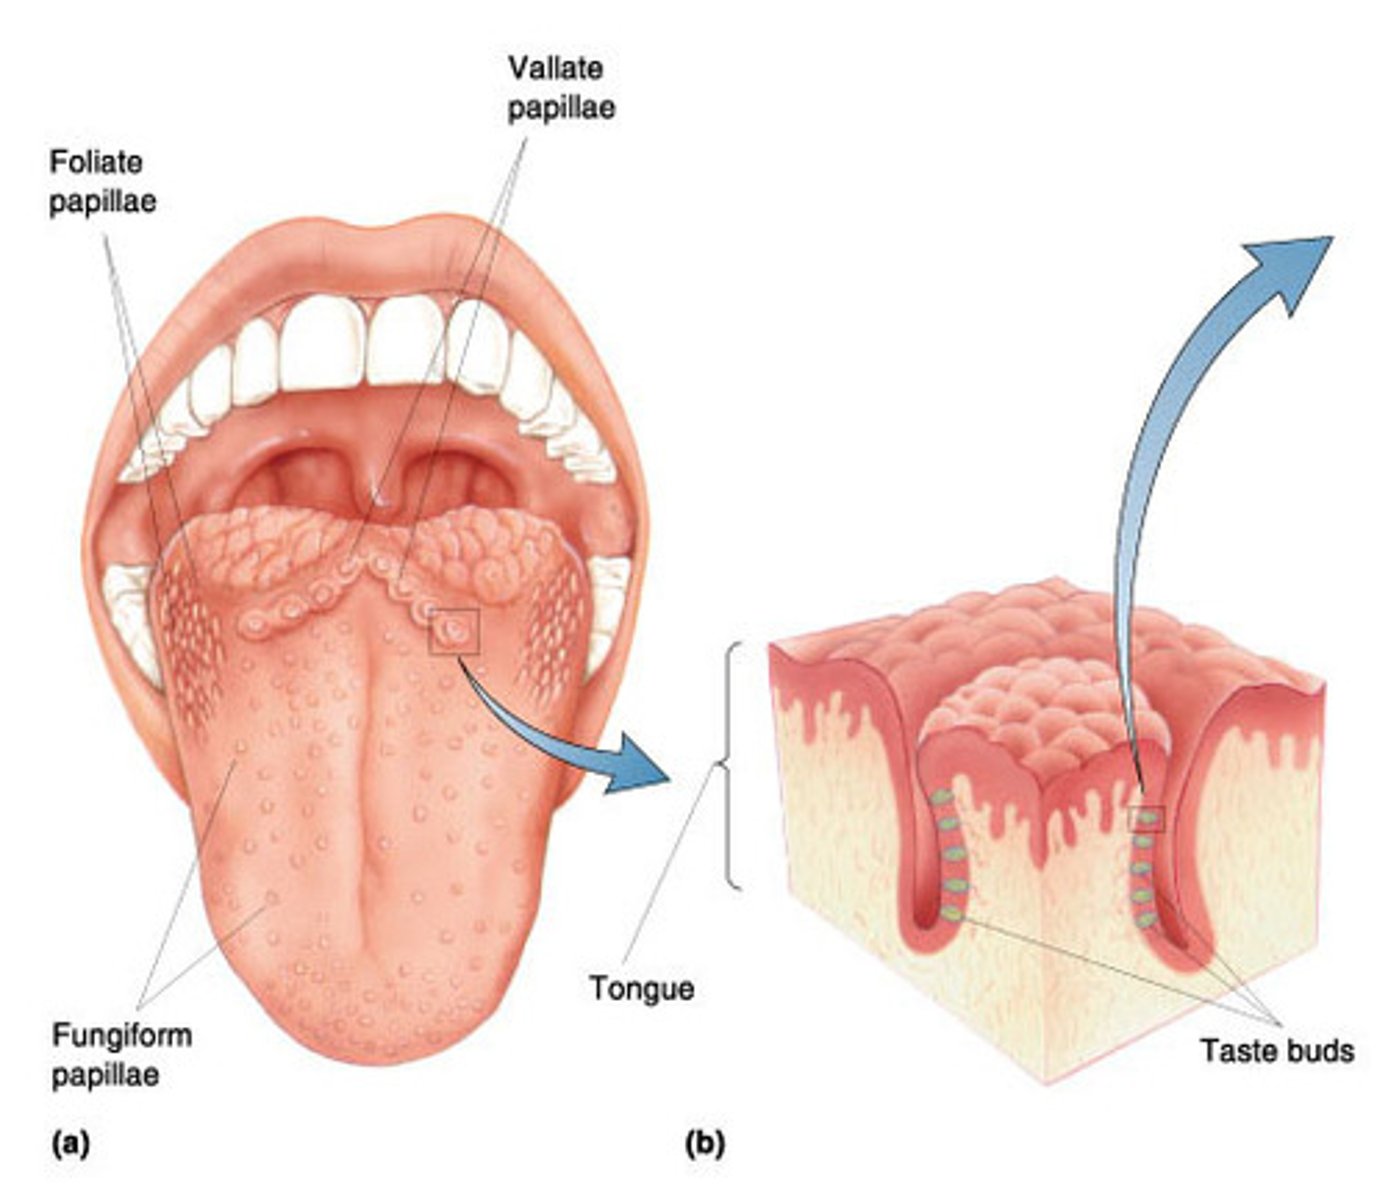

largest, least numerous arranged in inverted V shaped row at the back of the tongue?

does or does not have taste bud?

circumvillate papillae

does have taste buds